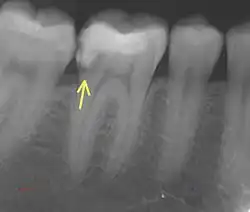

Sekundärkaries

Er bezeichnet eine erneute Kariesbildung an einer bereits behandelten kariösen Stelle, beispielsweise an einem überstehenden, ungenügend dichten oder schadhaften Füllungs- oder Kronenrand.